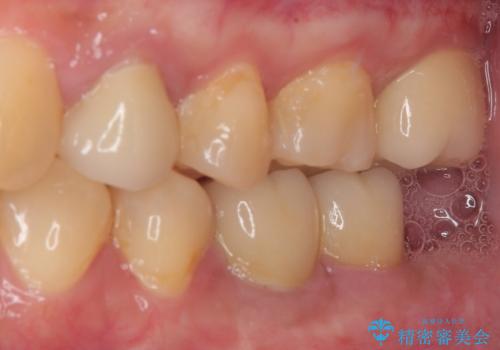

- 奥歯に物が挟まるとのことで来院された患者様です。

レントゲン写真より、奥歯2本に大きなむし歯があることが分かりました。

手前の歯はセラミックインレーで、奥の歯はオールセラミッククラウンにて治療を行うこととしました。

むし歯の範囲は大きかったですが、事前の症状もなく、処置後も一切の痛みなく快適に過ごすことができています。